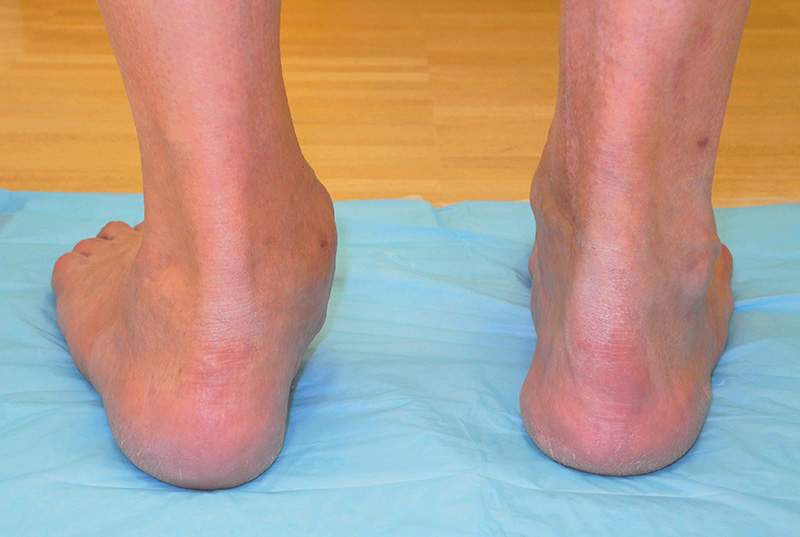

Rückfußachse

Die Längsachse des Fersenbeins weicht gegenüber der Längsachse des Unterschenkels um ca. 7° zur Außenseite ab (physiologischer Rückfußvalgus). Ist die Abweichung vermehrt, liegt ein Knickfuß vor, ist die Abweichung vermindert, oder kommt es gar zu einer Abweichung zur Innenseite, wird dies als Rückfuß varus bezeichnet. Genaue Grenzen, ab wann z.B. ein Knickfuß vorliegt sind nicht definiert. Eine Abweichung zur Innenseite ist aber in jedem Fall pathologisch.

Abbildung 6: Ausgeprägter Rückfußvalgus rechts, hier in Folge einer subtalaren Koalitio (J. Dohle).